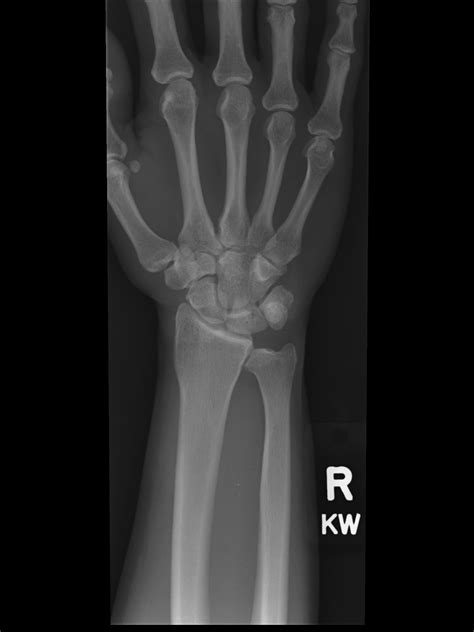

Diagnosing Positive Ulnar Variance requires more than a standard physical exam. Physicians typically rely on specific imaging techniques to accurately measure the variance. An X-ray of the wrist is the gold standard for diagnosis. However, how the X-ray is taken matters significantly.

To ensure accuracy, the patient's arm must be positioned correctly. If the arm is not properly aligned, the measurement of the ulnar variance can be falsely positive or negative. The doctor will likely request a posteroanterior (PA) view of the wrist with the forearm in a neutral position. In more complex cases, magnetic resonance imaging (MRI) may be utilized to evaluate the health of the surrounding soft tissues, such as the TFCC and the cartilage of the wrist bones, to see if damage has already occurred due to the impaction.

Because of the altered mechanics, this condition is frequently associated with Ulnar Impaction Syndrome. This syndrome describes the actual impingement of the ulna against the triquetrum and lunate (bones in the wrist) and the triangular fibrocartilage complex (TFCC), leading to degeneration of these structures.